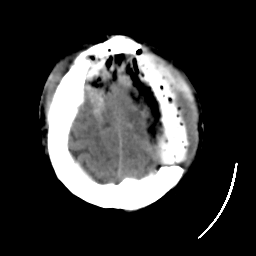

Meningioma: Roentgen-ray CT #1 -- Slice #20

[Home][Help][Clinical] Slice 20